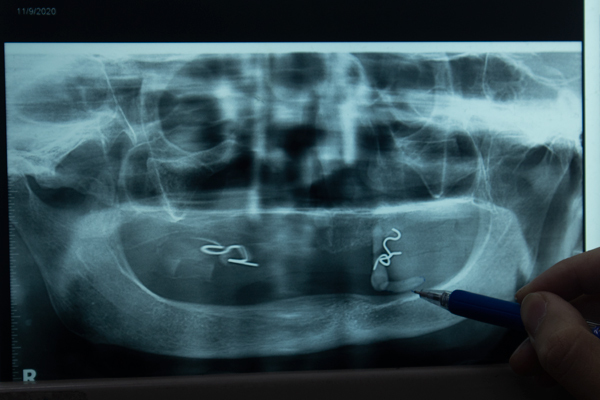

Hình ảnh viên sỏi trên phim chụp